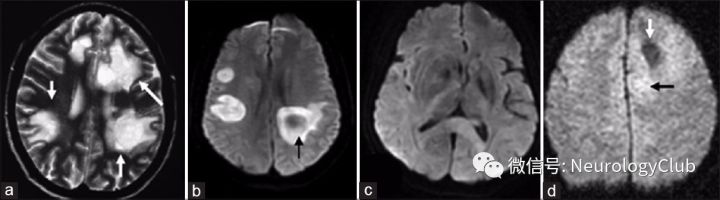

图2:轴位CT上的TDLs病灶:双侧半卵圆区大片状低密度灶(a);FLAIR序列:右侧半卵圆区大片状高信号影,左侧半卵圆区多发斑片状高信号影(b);T2WI:右侧半球大片状高信号影(c);T1增强:梳齿状强化,垂直于侧脑室(d

图3:轴位MRI FLAIR上可见蝴蝶状的TDLs病灶(a);轴位CT上同样的病灶表现为大片状稍低密度影(b);胼胝体III级星形胶质细胞瘤,胼胝体压部和双侧顶枕叶之间可见大片弥漫稍高密度影(c);PCNSL患者(弥漫性大B细胞淋巴瘤)轴位CT可见左侧基底节区“肾”形高密度病灶(d

图4:T2WI上多发圆形的TDLs病灶,即“煎蛋”征(a);DWI序列示双侧侧脑室旁TDLs病灶呈高信号,伴有环形弥散受限(b);DWI序列可见PCNSL胼胝体压部病灶弥漫稍高信号(c);III级间变性星形胶质细胞瘤患者, DWI序列上可见右侧额叶片状低信号灶,周围可见弥漫高信号影(d)

平扫时多数TDLs病灶呈低密度(图2a),少数为等密度(图3b),增强扫描时强化不明显。

1. MRI平扫:TDLs病灶常为T1WI低信号,T2WI高信号,较CT显示的病灶范围大。约70-100%TDLs患者的病灶在T2WI上为高信号,边界清楚(图5b),而少数病灶的边缘可见T2WI低信号(图4a)。大多数TDLs病灶具有占位效应(图1a,2b,2c,和3a),但较脑肿瘤轻,病灶周围常可见水肿。在急性或亚急性期,水肿主要为细胞毒性水肿,DWI序列上为高信号(图4b)。经激素治疗后,病灶可在数周内变小或消失。

2. 增强MRI:在急性期或亚急性期,由于血脑屏障的破坏,增强MRI可见不同模式的强化,如结节状、闭环、开环或火焰状强化。开环强化又称为C形强化(图5a),是最典型的,即病灶边缘不连续的半环形强化。对于部分TDLs病灶,扩张的小静脉形成梳齿状结构(图1b和2d),垂直于侧脑室,常见于急性期或亚急性期,是TDLs相对特异的影像表现,而未见于脑肿瘤。

在中国,一项纳入60例TDLs患者的研究显示TDLs的病灶呈动态变化,和病情进展相一致:(a)在急性期(起病时间≤3周),病灶为斑片状或结节状强化(图5c);(b)在亚急性期(起病4-6周),病灶逐渐演变为开环、闭环或花环状强化,可伴有斑片状强化(图5d);(c)在慢性期(起病7周后),病灶仍呈开环或闭环强化,强化逐渐减弱或消失。